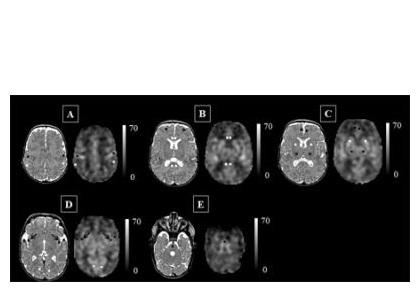

Les scientifiques aboutissent à des cartes du flux sanguin cérébral exprimé en mL / 100g / mn et montrent que, chez ces enfants, l'insula (flèches noires sur « D ») peut être particulièrement vulnérable aux stress supplémentaires de la vie. Ainsi, le flux sanguin cérébral de zones clés du cerveau peut être altéré chez les prématurés, ce qui peut constituer un signe précurseur d'une perturbation du développement cérébral bien avant que l'imagerie conventionnelle soit en mesure de la détecter.

Le débit sanguin cérébral, un bon marqueur du développement cérébral de l’enfant : ici, les chercheurs parviennent à cartographier, chez 98 nouveau-nés prématurés nés à moins de 32 semaines gestationnelles à la naissance et pesant moins de 1.500 grammes à la naissance, le débit sanguin cérébral, par imagerie par marquage de spins artériels. La technique non invasive identifie la concentration en eau du sang qui circule dans le cerveau des nourrissons afin d’identifier les zones qui reçoivent ou ne reçoivent pas le sang adéquat. Cette analyse montre que les nourrissons très prématurés présentent un débit sanguin cérébral cortical supérieur à celui des nourrissons nés à terme, mais que, dans certaines zones, dont l'insula -impliquée dans l'émotion-, le cortex cingulaire antérieur - impliqué dans les processus cognitifs- et le cortex auditif -impliqué dans le traitement du son- le débit sanguin est significativement diminué par rapport à celui de nourrissons nés à terme. Et, corrélées à ces déficiences de débit sanguin, sont identifiées des lésions cérébrales parenchymateuses.

« La maturation continue du cerveau du nouveau-né est illustrée par le schéma de distribution du flux sanguin cérébral. Grâce à cette technique d’imagerie, notre étude montre qu'en plus du tronc cérébral et de la matière grise profonde, l'insula et les zones du cerveau responsables des fonctions sensorielles et motrices sont également parmi les régions les plus oxygénées. Or, chez les nourrissons prématurés, l'insula peut être particulièrement compromise et donc vulnérable aux stress supplémentaires que l’enfant pourra rencontrer dans la vie. Ainsi, le développement altéré de l'insula et du cortex cingulaire antérieur chez ces nouveau-nés pourrait constituer les signes avant-coureurs du risque de troubles neurodéveloppementaux à long terme ».